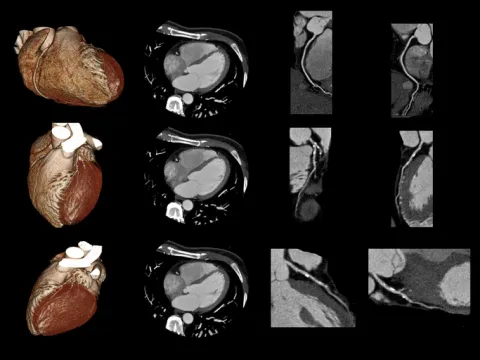

A mapping cardiac CT, sometimes abbreviated as a coronary CT, is a non-invasive imaging test that uses x-rays to create images of the heart. These images are then used to help guide our cardiac clinical electrophysiologists (EPs) with procedures, such as atrial fibrillation ablations and atrial flutter ablations, by providing a three-dimensional map of the anatomy of the heart.

This test helps provide a map of the anatomy of the heart. The data from this test is integrated into the mapping software that is used during an ablation to visualize the anatomy of the heart.